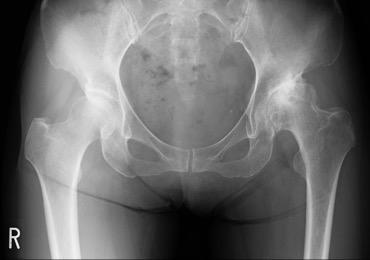

股関節は、大腿骨の骨頭と臼蓋という骨盤のくぼみからなる球関節(ボールと受け皿の関節)です。骨頭が臼蓋にはまり込む構造のため、足を様々な方向へ動かすことができます。関節の表面は軟骨に覆われ、関節のスムーズな動きを可能にしています。

加齢性の変化や外傷などにより軟骨が減少すると、すり減った軟骨の下のむき出しになった骨同士がこすれ合い、炎症が生じ痛みを感じます。

軟骨の減少により股関節の痛みが生じる疾患を変形性股関節症と呼びます。本邦における変形性股関節症の患者は約500万人とも言われ、多くの方がお悩みの疾患です。歩行中や階段昇降時の痛みや、関節の動かせる範囲が減少し靴下をはきにくい・正座ができないなどの症状を生じます。

加齢によって減少した軟骨は元に戻すことは出来ませんが、筋力トレーニングやストレッチなどのリハビリ、薬物療法、体重の減量などの保存療法が一般的に効果的です。保存療法で効果がなく、日常生活動作が著しく制限されている場合に、手術が必要になります。以下に代表的な手術療法である人工股関節全置換術(TKA)を説明します。

![]() 人工股関節全置換術前のレントゲン |